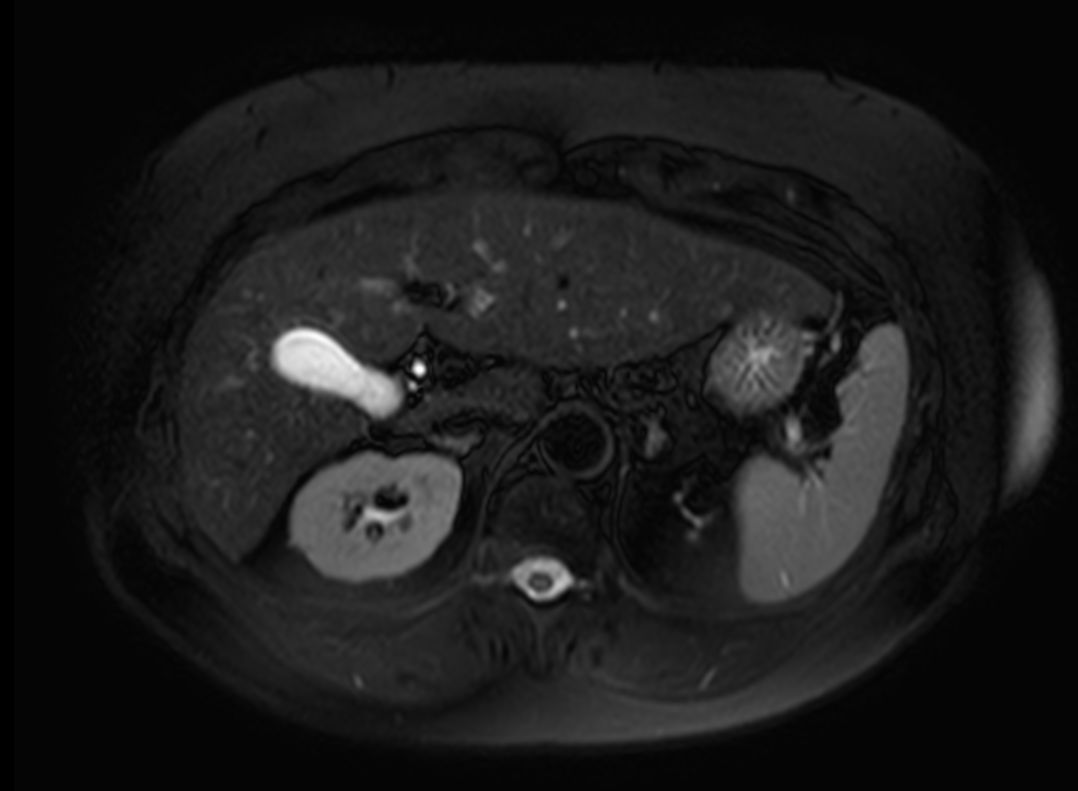

MR Elastography (SE-EPI, 4 slices)

-

MR Elastography (SE-EPI, 4 slices) (Stiffness Map)

MR Elastography (SE-EPI, 4 slices) (processing)